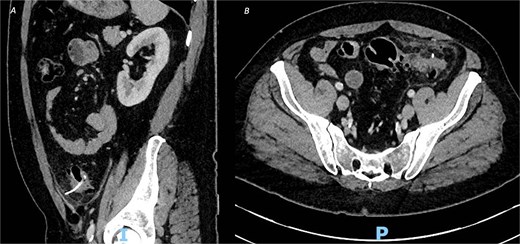

Post-operatively, the patient made a good recovery. As per local policy, he remained on intravenous antibiotics until discharge. In the immediate post-operative period, he was kept nil-by-mouth for 2 days and received total parenteral nutrition, before having his dietary intake increased after he passed flatus and opened his bowels. The patient was tolerating a normal diet by post-operative Day 5, with serial inflammatory markers also improving. A repeat CT scan on post-operative Day 8 confirmed resolution of the inflammatory changes with no evidence of leak or abscess formation (Fig. 2), and his intra-abdominal drains were subsequently removed.

CT of the abdomen and pelvic with contrast on post-operative Day 8 demonstrating resolution of the inflammatory changes with no evidence of leak or abscess formation, from (A) sagittal view and (B) axial view.